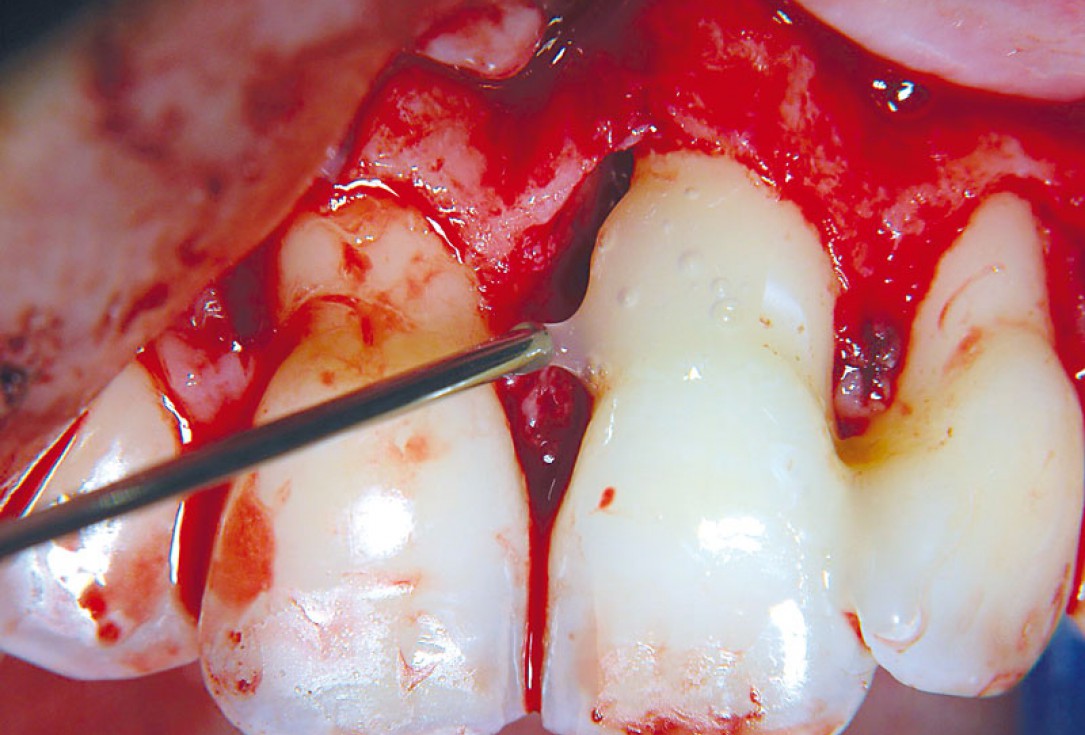

05/11 - Straumann® Emdogain® applied on the cleaned and pre-conditioned root surface.Non-contained intrabony defect treated using cerabone®, collprotect® membrane and Straumann® Emdogain® - Dr. T. Schwaar (2)